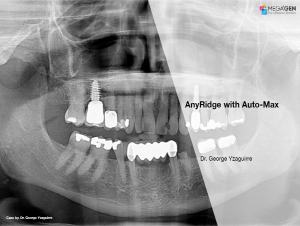

Keywords

e.g. product name, treatment solution, author, clinician name